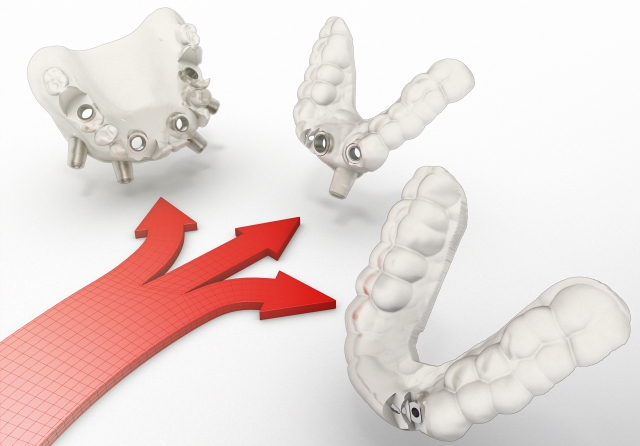

NOBEL GUIDE – ההייטק של הרפואה הדנטלית

NobelGuide היא תוכנה מיוחדת לביצוע השתלת שיניים בשיטת השתלה מתקדמת. השיטה פותחה במעבדות Nobel Biocare – החברה הדנטלית הגדולה והוותיקה ביותר בעולם. השתלת שיניים באמצעות NobelGuide מבוססת על הדמיה בתלת מימד בסיוע C.T.. הדמיה מיוחדת זו משפרת את הדיוק של השתלת שיניים ומאפשרת לרופא השיניים לתכנן מראש את מהלך ההשתלה ולבצע אותה במהירות, בדייקונות וביעילות. […]

במרכז הרב תחומי בניהולו של ד"ר יורם רוזן התמסדה שגרה של קביעת הישגים דנטאליים מרשימים מדי שבוע בשבוע. ד"ר רוזן, בעל 20 שנות ניסיון ברפואת שיניים מתקדמת ושיקום הפה, השתלם אצל גדולי המומחים בעולם בטכנולוגיות החדשניות ALL ON 4 ו"נובל גייד" (Nobel Guide), הנחשבות להייטק של רפואת השיניים בעולם, ונבחר על-ידי ד"ר פאולו מאלו להיות […]

העמסה מיידית (Immediate function) על לסת חסרת שיניים באמצעות ארבעה שתלים

אחד המושגים שמשנים בשנים האחרונות את פני השיקום הדנטאלי הוא "העמסה מיידית" Immetidate implant function, שיטת השתלה שהפכה למתודת טיפול מקובלת ונפוצה יותר ויותר, למטרות שיקום קבוע של מערכות שיניים שלמות, במקרים בהם חסרות כל השיניים בלסת. הפרוטוקול המקורי, עם הניסיון המצטבר הרב ביותר בעולם בתחום זה, הוא הפרוטוקול של ד"ר פאולו מאלו, אותו אימצתי […]